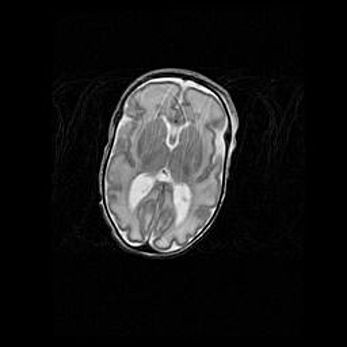

Лейкомаляция с кистозно-глиозной дегенерацией головного мозга.

Возраст: 2 месяца 25 дней

Вес: 6400 г

Окружность головы: 40 см

Срок гестации: 41 неделя

Лейкомаляцию относят к ишемически-гипоксическим повреждениям головного мозга, диагностируемым у новорожденных. При лейкомаляции в головном мозге обнаруживают очаги некроза, возникшие после тяжелой гипоксии и нарушения кровотока. В процессе морфогенеза очаги проходят три стадии: 1) развития некроза, 2) резорбции и 3) формирования глиозного рубца или кисты. Перивентрикулярная лейкомаляция (ПЛ) встречается примерно в 12% случаев среди новорожденных, обычно – у недоношенных детей, причем, частота ее зависит от массы, с которой младенец появился на свет. Наибольшее число малышей страдает лейкомаляцией, если масса при рождении 1500-2500 г.